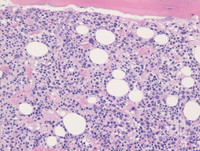

Bone marrow core biopsy

The first two images correspond to the bone marrow core biopsy from the procedure performed at the outside institution demonstrating dysplastic megakaryocytes and some background hematopoiesis in addition to increased mononuclear immature lymphoid cells.

The last image corresponds to the in-house bone marrow biopsy performed after admission demonstrating isolated lymphoid component present in a background of markedly damaged and edematous bone marrow without any background hematopoiesis.